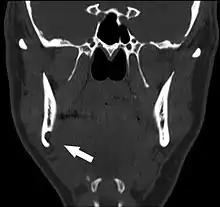

Stafne's defect is usually discovered by chance during routine dental radiography.[4] Radiographically, it is a well-circumscribed, monolocular, round, radiolucent defect, 1–3 cm in size, usually between the inferior alveolar nerve (IAN) and the inferior border of the posterior mandible between the molars and the angle of the jaw. It is one of the few radiolucent lesions that can occur below the IAN. The border is well corticated and it will have no effect on the surrounding structures. Computed tomography (CT) will show a shallow defect through the medial cortex of the mandible with a corticated rim and no soft tissue abnormalities, with the exception of a portion of the submandibular gland. Neoplasms, such as metastatic squamous cell carcinoma to the submandibular lymph nodes or a salivary gland tumour, could create a similar appearance but rarely have such well defined borders and can usually be palpated in the floor of the mouth or submandibular triangle of the neck as a hard mass. CT and clinical exam is typically sufficient to distinguish between this and a Stafne defect. The Stafne defect also tends to not increase in size or change in radiographic appearance over time (hence the term "static bone cyst"), and this can be used to help confirm the diagnosis.[4] Tissue biopsy is not usually indicated, but if carried out, the histopathologic appearance is usually normal salivary gland tissue. Sometimes attempted biopsy of Stafne defects reveals an empty cavity (possibly because the gland was displaced at the time of biopsy), or other contents such as blood vessels, fat, lymphoid or connective tissues. Defects of the anterior lingual mandible may require biopsy for correct diagnosis at this unusual location.[2] The radiolucent defect here may be superimposed on the lower anterior teeth and be mistaken for an odontogenic lesion. Sometimes the defect may interrupt the contour of the lower border of the mandible, and may be palpable. Sialography may be sometimes used to help demonstrate the salivary gland tissue within the bone.